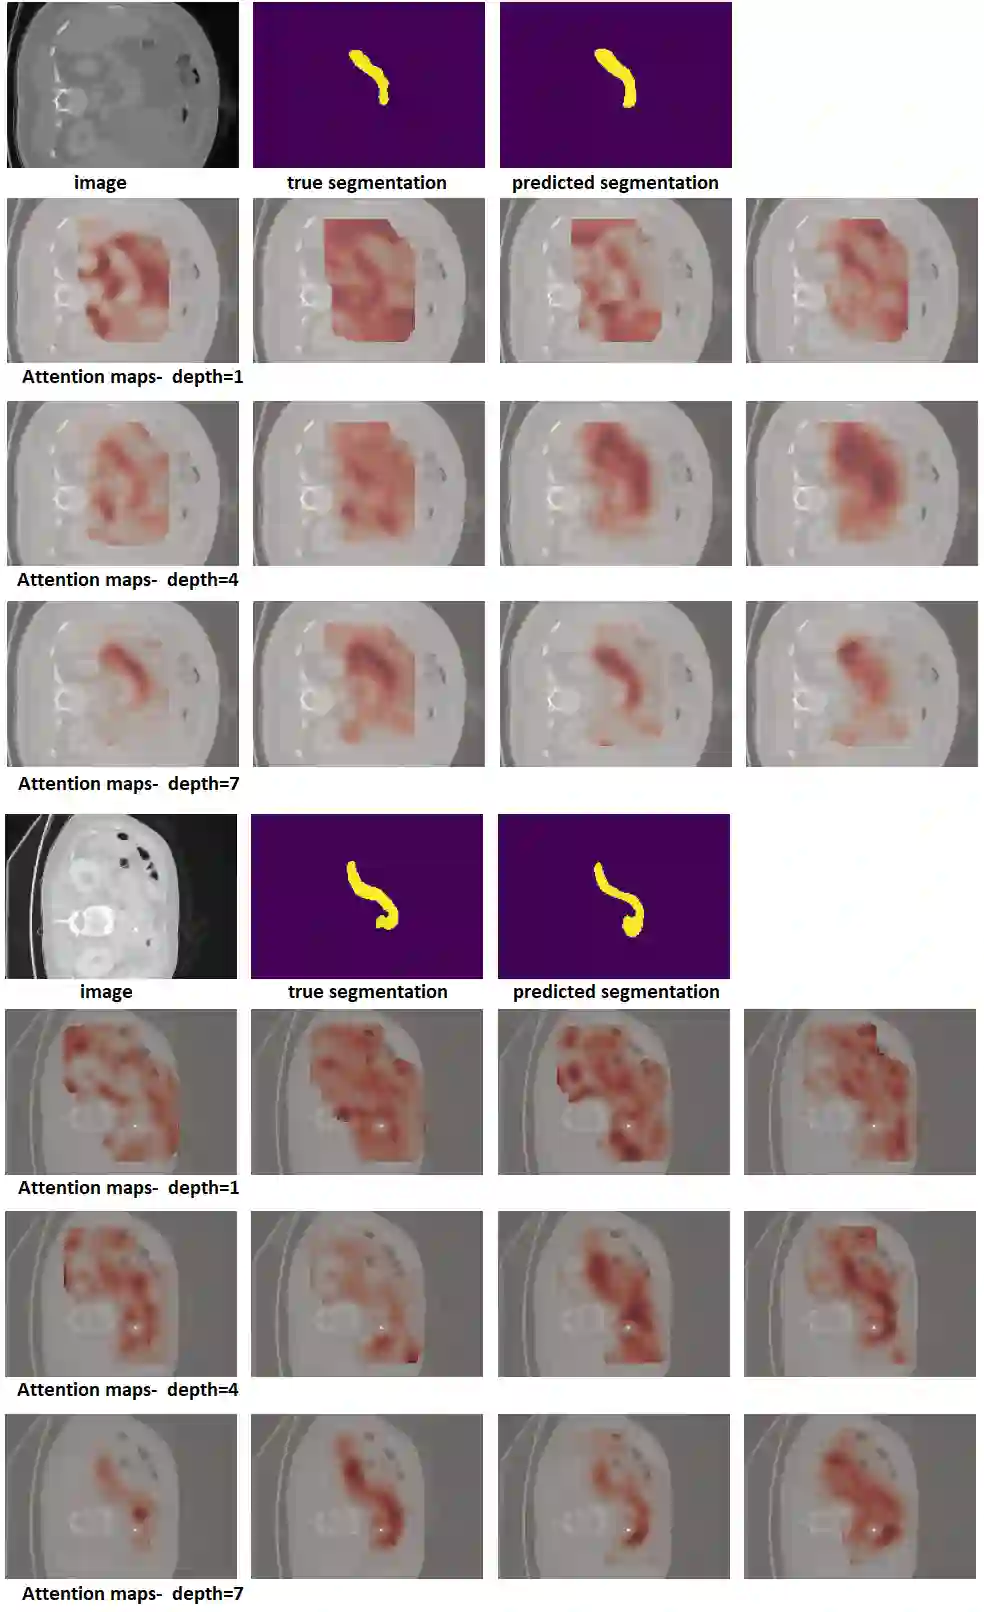

Like other applications in computer vision, medical image segmentation has been most successfully addressed using deep learning models that rely on the convolution operation as their main building block. Convolutions enjoy important properties such as sparse interactions, weight sharing, and translation equivariance. These properties give convolutional neural networks (CNNs) a strong and useful inductive bias for vision tasks. In this work we show that a different method, based entirely on self-attention between neighboring image patches and without any convolution operations, can achieve competitive or better results. Given a 3D image block, our network divides it into $n^3$ 3D patches, where $n=3 \text{ or } 5$ and computes a 1D embedding for each patch. The network predicts the segmentation map for the center patch of the block based on the self-attention between these patch embeddings. We show that the proposed model can achieve segmentation accuracies that are better than the state of the art CNNs on three datasets. We also propose methods for pre-training this model on large corpora of unlabeled images. Our experiments show that with pre-training the advantage of our proposed network over CNNs can be significant when labeled training data is small.